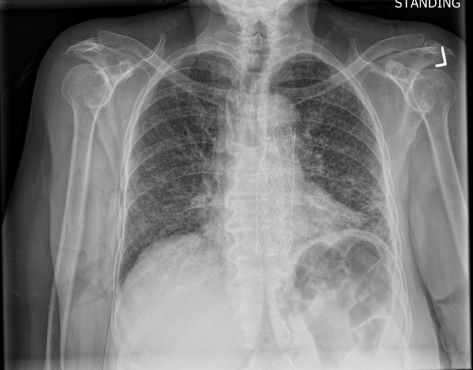

This is the chest X-ray during this current hospitalization…

Burn this image into your head! This is a classic miliary pattern on a chest radiograph! The term miliary stems from millet seed, a term used to describe a group of small-seeded species of cereal crops or grains

Subsequent chest CT revealed innumerable bilateral pulmonary nodules, which were not present a month prior.

- Chest radiograph: Classic faint reticulonodular infiltrate uniformly throughout lungs.